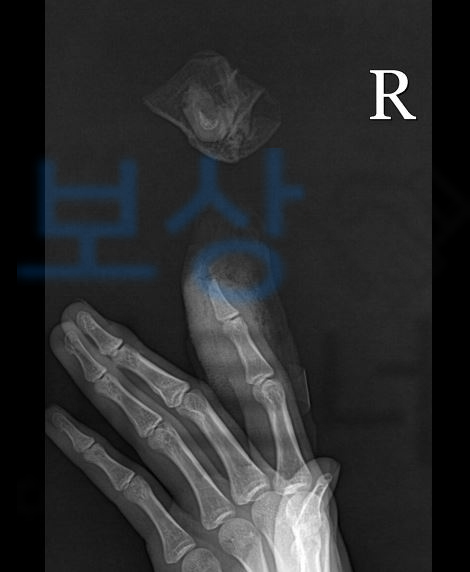

이로인해 검지손가락의 뼈까지 일부분 절단되는 사고를 당하셨고 바로 접합술을 시행하게 되었죠.

재접합술을 시행받았으며, 약 6주 진단을 받아 요양해야하는 상황이었습니다. 먼저 근무 중 당한 사고이기에 산재보험처리를 진행하실 수 있고 산재보험은 사회보험기이게 무과실책임주의에 따라 근무자의 과실 상관없이 산재 보험에서 보상 가능합니다.